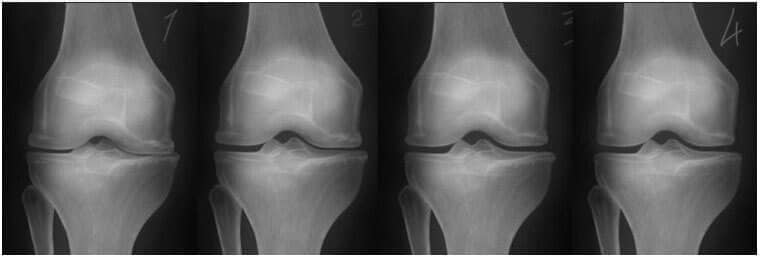

- rádiografický obrázok nižšie ukazuje typický obraz obnovy kolenného kĺbu.